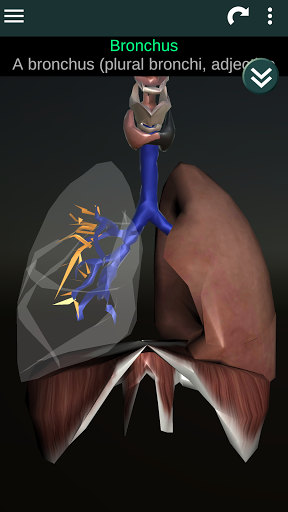

* Sistem pernafasan, yang meliputi trakea, bronkus, paru-paru dan animasi sistem ini.

* Deskripsi masing-masing organ.